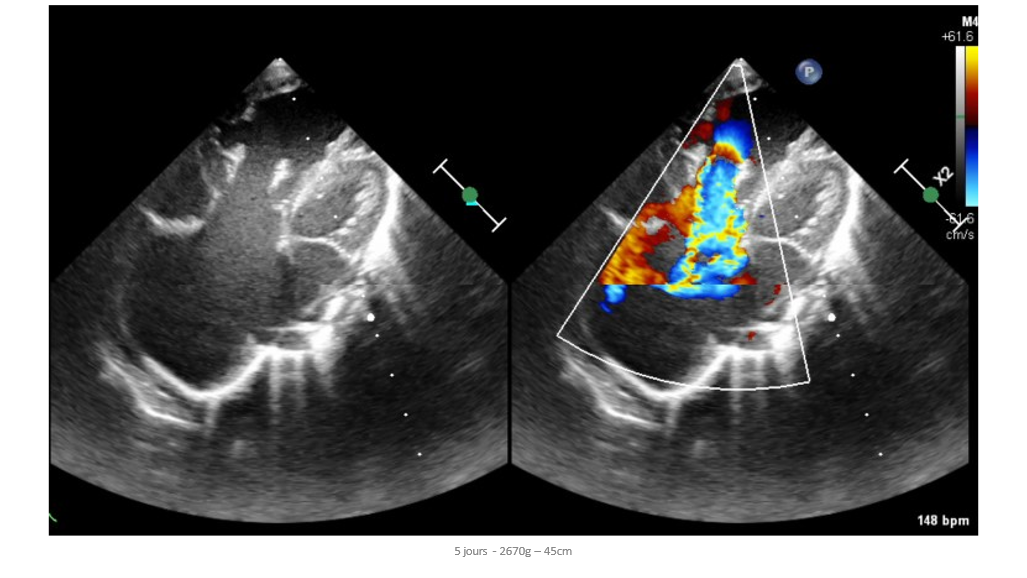

A 5-day-old newborn, born at 36 weeks of gestation to a mother with preeclampsia, presented with poor initial adaptation, including no movement, no cry, and a heart rate below 100 bpm. Echocardiography revealed a major defect in the atrioventricular valve with torrential regurgitation, tricuspid atresia with absence of flow through the right ventricular outflow tract, and a well-developed pulmonary artery. The newborn was started on prostaglandin therapy, which allowed for pulmonary perfusion with oxygen saturation between 85-90%. A multidisciplinary team discussed three possible management options: dilation of the right ventricular outflow tract, Starnes procedure with Blalock shunt, or discontinuation of prostaglandin therapy.

- *Echocardiography Findings:*

- Major defect in atrioventricular valve with torrential regurgitation

- Tricuspid atresia with absence of flow through the right ventricular outflow tract

- Well-developed pulmonary artery

- Large atrial septal defect (ASD) with right-to-left shunt

- Large patent ductus arteriosus (PDA) with left-to-right shunt

- No left-sided anomalies